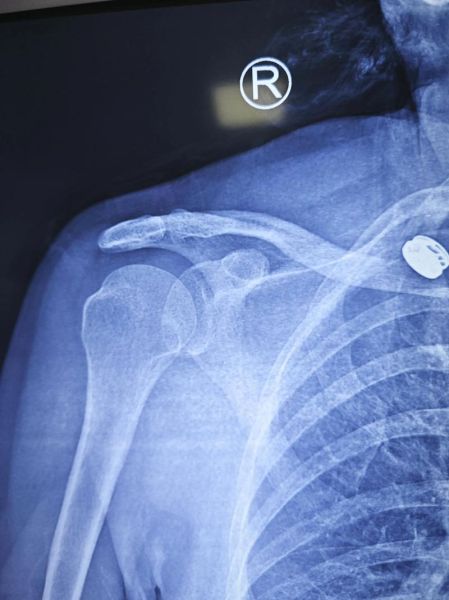

宝宝肩膀脱臼,医学上称为“肩关节脱位”或“桡骨头半脱位”,在婴幼儿阶段并不罕见。很多家长第一次遇到时都会惊慌失措:孩子突然大哭、手臂垂着不动,却又看不到明显外伤。到底哪些表现提示肩膀脱臼?家长在家能做哪些初步判断?以下内容用问答+分块的方式,一次性讲透。

(图片来源网络,侵删)

Q2:脱臼和骨折怎么区分?

骨折通常伴随:

• 明显肿胀或瘀青

• 局部骨擦音

• 拒绝任何方向的活动

而脱臼多表现为特定姿势固定、被动活动尚可但疼痛加剧。最保险的做法仍是去医院拍片排除骨折。